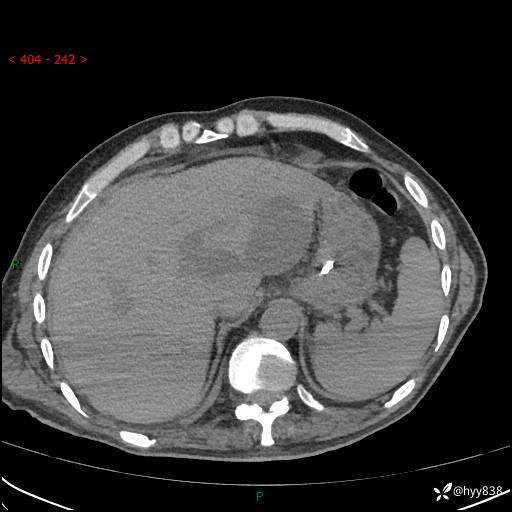

腹部CT平扫

增强